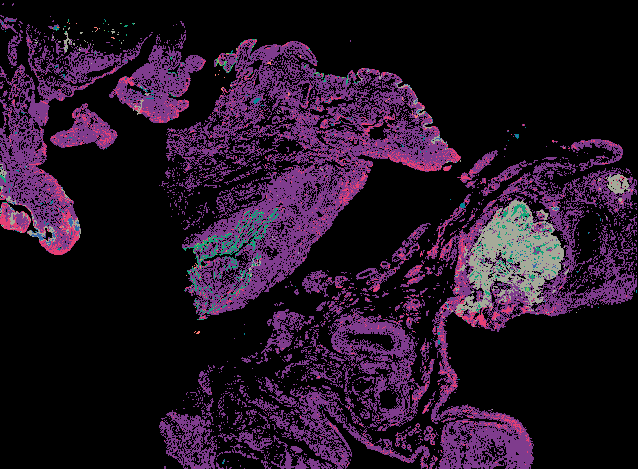

Serous Tubal Intraepithelial Carcinoma (STIC) with BRCA2 Mutation (LSP18251) from 'Multimodal Spatial Profiling Reveals Immune Suppression and Microenvironment Remodeling in Fallopian Tube Precursors to High-Grade Serous Ovarian Carcinoma'.